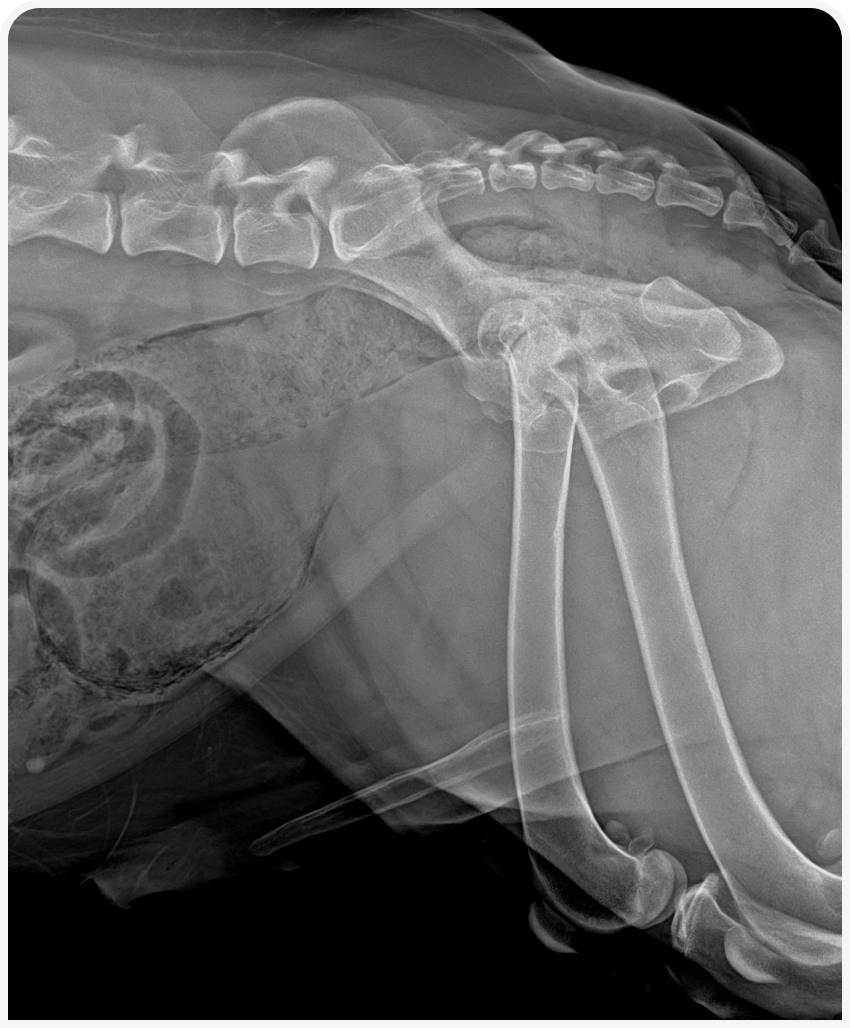

Рисунок 1. Рентгеновский снимок брюшной полости и области уретры в боковой проекции пациента с эмфизематозным циститом.

В ходе обследования мы можем обнаружить локальное скопление газа в стенке мочевого пузыря. А также столкнуться с трудностями в визуализации мочевого пузыря из-за тотального присутствия газа в стенках мочевого пузыря и артефактов изображения. Присутствие газа также может быть выявлено в уретре, из редка может быть выявлен газ в почечных лоханках и в тканях простаты у кобелей.

Интактный кобель 8 лет, вес 50 кг доставлен в клинику в связи с макрогематурией.

Осмотр не примечателен, пациент стабилен. Месяцем ранее проведена кастрации в связи с доброкачественной кистозной гиперплазией простаты. Выявлено присутствие газа в стенке мочевого пузыря и уретры. Исключен сахарный диабет, протеинурия ранее не выявлялась.